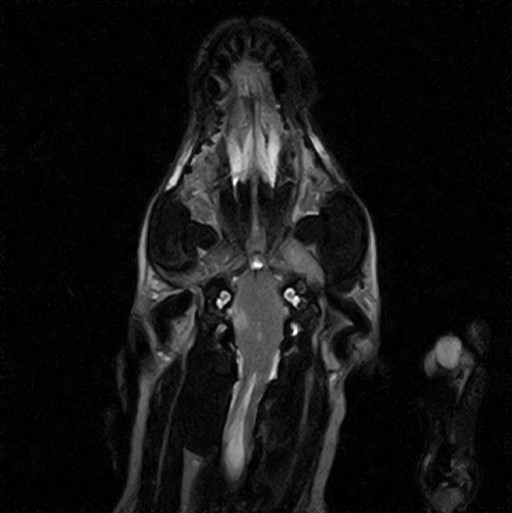

W obrębie mózgowia i trzewioczaszki najczęstszymi wskazaniami do badania MRI są:

• patologie w obrębie oczodołów i struktur przyległych – ocena zmian pourazowych, zapalnych i nowotworowych

• zmiany zaoczodołowe i około zębowe – diagnostyka przewlekłych infekcji